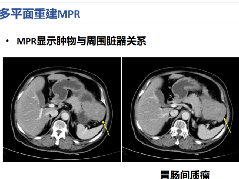

影像学特点:界限明确的圆形肿块伴有大量、低密度的囊性坏死区域是良性 PS 最常见的 CT 表现。

AntoniA 型患者有低密度、实性肿块,不均匀或很少有多隔强化。AntoniB 型为均匀性囊性或多分隔性肿块。此外,先前的研究发现,血管内血栓形成发生在

Antoni B 区,导致坏死和囊肿的发展。既往研究结果显示,胰腺神经鞘瘤的大小分别为(1.5-20 cm)、囊性肿瘤(3.0-20 cm)和实体瘤(1.5-3.5 cm)。界限清晰的圆形肿块和大量的、低密度的囊性坏死区域是良性胰腺神经鞘瘤最常见的 CT 表现。恶性肿瘤表现为快速发展,侵犯周围组织,轮廓不均匀的实体不均匀肿块的强烈增强,以及血管血栓形成。

MRI 显示,典型的神经鞘瘤被包膜包裹,T1 加权图像低信号,T2 加权显示不均匀高信号。MRI 通常可以勾画出肿瘤的血管受累程度,更好地分析胰腺病变和胰管,肿块有包膜,胰腺导管无钙化或扩张。

大多数胰腺神经鞘瘤具有明显的退行性改变,包括囊肿形成、钙化、出血、透明化和黄质瘤浸润。因此,胰腺神经鞘瘤在影像学检查中常表现为囊性、坏死性和出血性肿块。最重要的问题是难以做出正确的术前诊断。胰腺神经鞘瘤的临床放射学表现与胰腺囊性肿瘤相似。